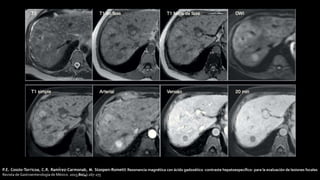

P.E. Cossio-Torricoa, C.R. Ramírez-Carmonab, M. Stoopen-Rometti Resonancia magnética con ácido gadoxético -contraste hepatoespecífico- para la evaluación de lesiones focales

Revista de Gastroenterología de México. 2015;80(4):267-275